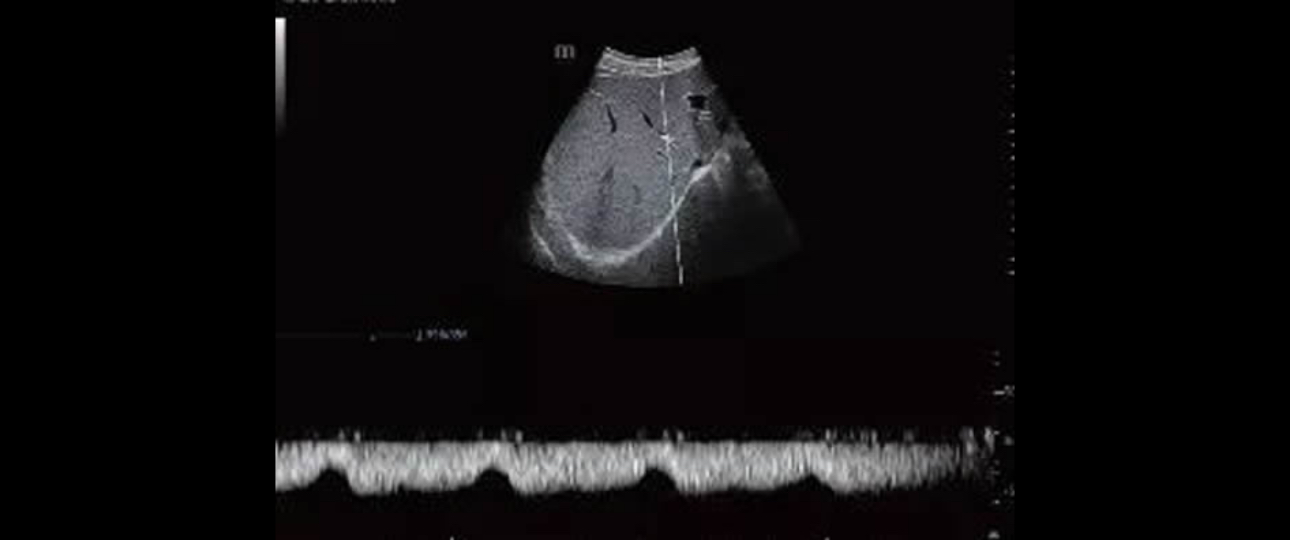

To their surprise, a bright liver with smooth margins and patent portal vein has been found using the B-mode and Doppler of MindrayŌĆÖs Resona 7. Moreover, the mean portal blood flow velocity was 28 cm/s and the flow in the hepatic veins had a biphasic pattern.[2]

Applying with the Sound Touch Elastography, the system showed a median value of 8.83 kPa (IQR/M = 1.8%) which indicated significant fibrosis. The liver stiffness measurement was also reliable.

Transient elastography with a FibroScan device was performed in the same session soon after the evaluation with the Resona 7 and the values obtained was 8.5 kPa. Liver biopsy, performed a week later, showed stage 2 fibrosis.[3]

With availability of an ultrasound system, in which shear wave elastography technique is implemented, experts were able to evaluate the liver stiffness whose results were compatible with significant fibrosis (F2), confirmed by liver biopsy later.